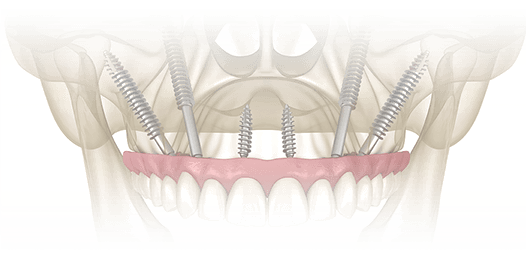

ザイゴマインプラント Zygoma Implants

ザイゴマインプラントは、骨が不足している上顎に対して頬骨(ザイゴマ)を利用して固定する手法で、骨移植を行わずに治療が可能になる場合があります。これにより、従来は手術が難しいとされていた方にも対応の幅が広がっています。

骨が極端に薄いケースでも可能なザイゴマインプラント

骨が極端に薄いケースでも可能なザイゴマインプラント イメージ01

骨が極端に薄いケースでも可能なザイゴマインプラント イメージ02

ザイゴマインプラントは、標準的なインプラントより長いインプラント体を使用し、顎骨ではなく頬骨下側に固定することで、上顎にほとんど骨がない場合や骨が極端に薄いケースにも対応できる選択肢として注目されています。この手法では、手術当日に仮歯を装着し、すぐに噛む機能を回復できるよう設計されています。

通常、ザイゴマインプラントは上顎の後方部分に埋入されます。さらに、骨吸収が特に重度の場合には、両側に2本ずつザイゴマインプラントを埋入することもあります。これにより、従来は治療が難しかった症例でも、安定した咬合と審美性を実現できます。

• 上顎インプラント2本とザイゴマ2本によるオールオン4

術前

術後

年齢・性別 67歳・男性

治療期間 オペから上部セットまで5ヶ月、通院回数17回

治療費用 3,021,040円(税込)

治療内容 右上前歯が痛みがあり来院。本人の希望は入れ歯にはしたくない、歯がない時期があると困る、他院ではインプラントはできないといわれたとのことで、抜歯・インプラントオペ当日に歯まで入るオールオン4を希望。